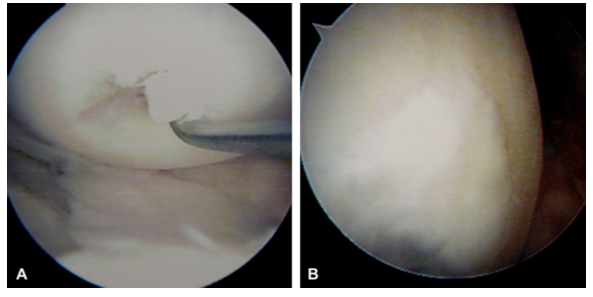

A圖這是一個軟骨損傷的案例,20*30mm的損傷面積,B使用UCF7個月後修復的效果。

A圖看著很恐怖,但是更真實,這就是我們的膝關節的內部,受損嚴重,B 使用UCF修復12個月後的效果

緊接著由Aiko Wang女士結合Peter先生的介紹,給大家分享了UCF對膝關節修復典型案例,比如81歲老人膝關節損傷及老年退行性病變的介紹及分享。世界著名橄欖球運動員,新西蘭冰球運動員關節損傷修復的案例分享等等。所有真實體驗過UCF神奇修復效果的受益者都用驚奇的口吻描述自己的親身感受並給以UCF的膝關節修復效果表示認可。